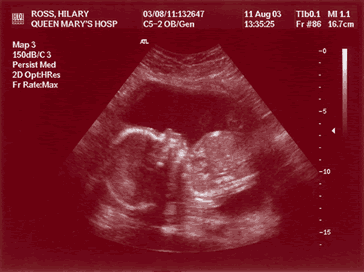

21 week scan